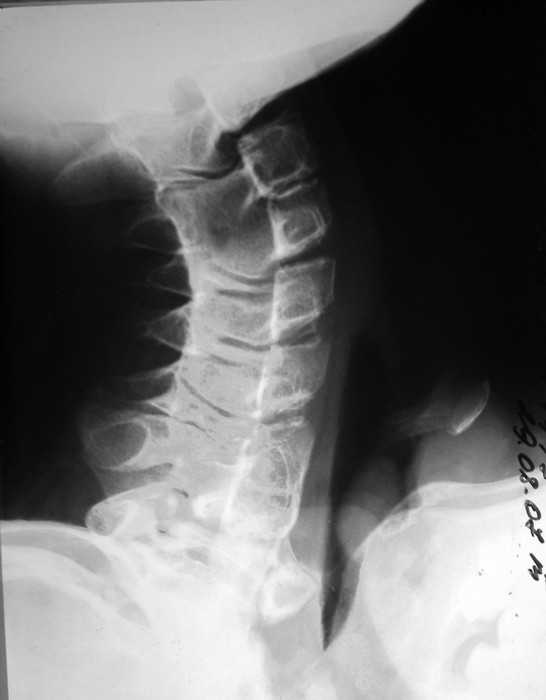

Врожденная аномалия, множественные экзостозы

Место болезни: при осмотре определяется - вынужденное положение верхних конечностей в плечевых и локтевых суставах, множественные опухолеподобные образования вдоль позвоночника и по наружной поверхности верхней трети левой бедренной кости округлой формы, с четкими контурами, неподвижные, безболезненные, каменистой плотности. приводяще-отводящая контрактура в обеих плечевых суставах, сгибательно-разгибательная контрактура в обеих локтевых суставах с сохранение про- и супинационных движений. Объем движений в пальцах кисти и лучезапястных суставах в полном объеме без ограничений, безболезненный.

Диагноз: врожденная аномалия развития шейного отдела позвоночника с резким нарушением функции в плечевых и локтевых суставах, множественных костно-хрящевые экзостозы, оссифицирующий миозит.

рентгенограммы

это fibrodysplasia ossificans progressiva, генетически обусловленная прогрессирующая метаплазия соединительной и мышечной ткани в костную. Лечится (вернее, тормозится) консервативно, после попыток оперативного лечения и после травм - прогрессирует.